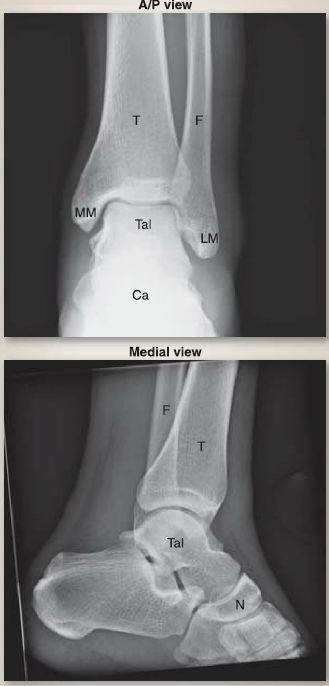

Figure 8: Plain film radiographs of normalankle. A/P = anterior/posterior, Ca = calcaneus, F = fibula, LM = lateral malleolus, MM = medial malleolus, N = navicula, T = tibia, Tai= talus.